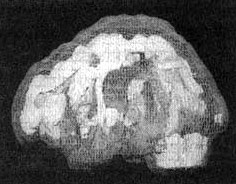

Мозг Роба. Результаты сканирования SPECT

Трехмерное изображение — активный мозг, вид сверху.

После лечение Anafranil. Активность поясной системы нормализовалась.

После трех лет неуклонного улучшения состояния на фоне приема Anafranil (оба раза, когда предпринимались попытки снизить дозу, симптомы возвращались), повторное сканирование показало нормализацию функции мозга.